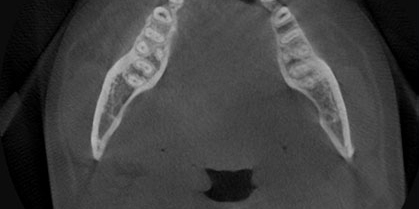

Less is Better

Low Dose

Just scan the only area where you need. Minimize x-ray radiation dose.

70μm resolution @ 4x3cm